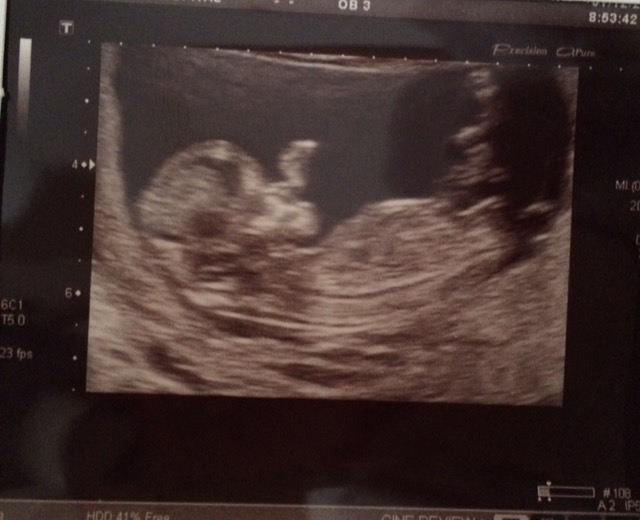

Which exact gestation is this? Girly guess for now.

Leaning blue [emoji170]

Leaning blue on this one

Tricky nub. Shape looks girly but slight angle. Maybe girl

Leaning girl 💖 xxxxxx

Girl!